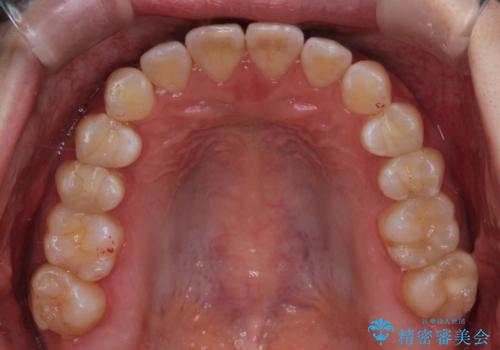

前歯と奥歯のガタガタを矯正で改善

- 患者様は、前歯と奥歯のガタガタ(叢生)を改善し、正面から見た時の歯並びを美しく整えたいとのご要望で来院されました。診断の結果、非抜歯での矯正が可能と判断し、インビザラインを使用する治療計画を立案しました。透明な矯正装置で目立ちにくい治療を行いながら、前歯と奥歯の両方を整列させることを目標にしました。

インビザラインを用いて、前歯の見た目を重視しつつ、奥歯のガタガタも改善しました。特に正面から見た際の美しい歯列を意識し、段階的に歯を移動させることで、全体の調和を図りました。治療中は、適切な装着時間を守ることや、装置の清潔を保つことが重要でした。また、歯肉や歯列全体に無理な負担がかからないように移動を管理しながら治療を進めました。結果として、前歯と奥歯がきれいに並び、見た目にも機能的にも満足いただける仕上がりとなりました。